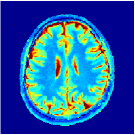

VI-E In-vivo experiments

Two sets of experiments were conducted here: first, we used the 2D and 3D acquisition sequences for scanning a healthy volunteer’s brain (real-world acquisitions). Figures 6 and 7 display the parametric maps reconstructed from 2D spiral and radial readouts. We computed the T1, T2 and proton density (PD) maps using baseline reconstruction algorithms ZF, VS, LR, FLOR, AIR-MRF and our proposed LRTV. While baselines use DM either for quantitative inference or also during reconstruction (i.e. AIR-MRF), we further compare the DM-free LRTV’s performance when cascaded to DM, KM and MRFResnet for quantitative inference. For the 3D spiral acquisitions we compared LRTV and its closest competitor VS in Figure 8. Outcomes from other tested algorithm are displayed in the supplementary materials (Figure S5). Since FLOR does not use dimensionality-reduction, our system ran out of memory during 3D reconstruction; hence results are not reported in this case.

VI-E1 Discussion

The LRTV-DM and LRTV-MRFResnet perform on par, and both outperform all tested baselines for reconstructing T1, T2 and PD maps in all acquisition schemes. This can be observed both visually in Figures 6, 7, 8, S2 and S3, and quantitatively in Table IV across all tested metrics. Other baselines were unable to successfully remove the under-sampling artefacts in TSMIs, and these errors propagated to the parameter inference phase and resulted in inaccurate maps. Temporal-only priors incorporated within LR are shown insufficient to regularise the inverse problem and LR sometimes (e.g. 2D spiral acquisitions) can admit solutions with even stronger artefacts than the model-free ZF baseline. This issue was previously studied for other non-Cartesian MRF readouts that similar to our spiral/radial trajectories, miss to sample the corners of the k-space in all timeframes (see section 2.2.2 and figure 2 in [19]). In the absence of reference for the k-space corners information, the LR iterations despite minimising the objective can converge to solutions with high-frequency artefacts, as visible in the computed maps. This highlights the need for adding an appropriate spatial-domain regularisation. FLOR reduces the LR’s artefacts but this improvement is limited because the suggested nuclear norm penalty does not incorporate an explicit spatial regularisation. Further for reducing artefacts, FLOR can introduce an undesirable bias in the computed T1/T2 maps e.g. see error maps in Figures S2 and S3. The non model-based VS baseline incorporates spatial regularisation and results in spatially smoother maps than ZF and LR, but it is unable to output artefact-free images. Further and consistent with our in-vitro experiment, we observe that VS overestimates the T2 values (e.g. in White and Grey matter regions) in tested 2D acquisitions i.e. the spatial regularisation trades off agains the quantification accuracy. The model-based AIR-MRF adds spatial regularisation through 2D/3D low-pass Gaussian filters however this trades off the sharpness of the computed maps and can increase the errors at the tissue boundaries (we searched Gaussian spreads that keep the blurs and high-frequency artefacts minimal). For our acquisition readouts, Gaussian filters performed better than disk filters of [19] for avoiding strong Gibbs artefacts. On the other hand, the spatiotemporally regularised LRTV greatly improves the TSMI reconstructions i.e. 4 dB enhancement compared to the closest competitor baseline (Table IV). This enables computing accurate and aliased-free multi-parametric inference using DM or the DM-free learning-based alternative MRFResnet as visible in Figures 6, 7, 8, S2 and S3. MRResnet and DM score competitive quantitative inference results i.e. T1 and T2 MAPE less than 5% and 9%, respectively (Table IV). KM also outputs comparably accurate T1 maps, however this shallow learning model despite having a model size larger than MRFResnet, is unable to learn accurate T2/PD quantification and it results in poor estimated maps, consistent with our observations in section VI-C.